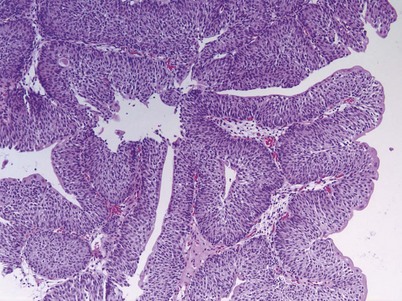

Urothelial papilloma is a benign proliferative growth in the bladder that is composed of delicate stalks lined by normal-appearing urothelium (Fig. 80–2) (Montironi and Lopez-Beltran, 2005). Papillomas had previously been categorized as grade 1 Ta tumors of the bladder until the World Health Organization (WHO) changed the classification of noninvasive bladder cancer in 1998 (Epstein et al, 1998). Papillomas rarely have mitotic figures and lack markers of aggressive growth such as TP53 or RB mutations, but 75% of these tumors will have mutations in the fibroblast growth factor receptor-3 (FGFR-3) (van Rhijn et al, 2004). Papillomas may recur, but they do not progress or invade.